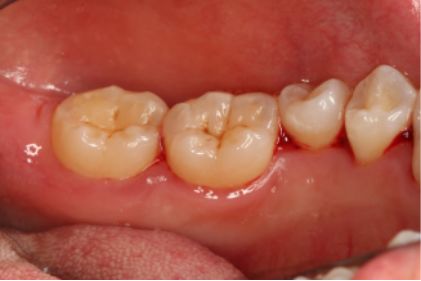

采用PT5牙周治疗仪进行全口超声龈上洁治术、超声龈下刮治术。术后5周复查可见牙龈炎症明显减轻,仍有轻度炎症,复查发现患者口腔卫生维护欠佳,再次进行口腔卫生宣教。

超声洁刮治术后5周